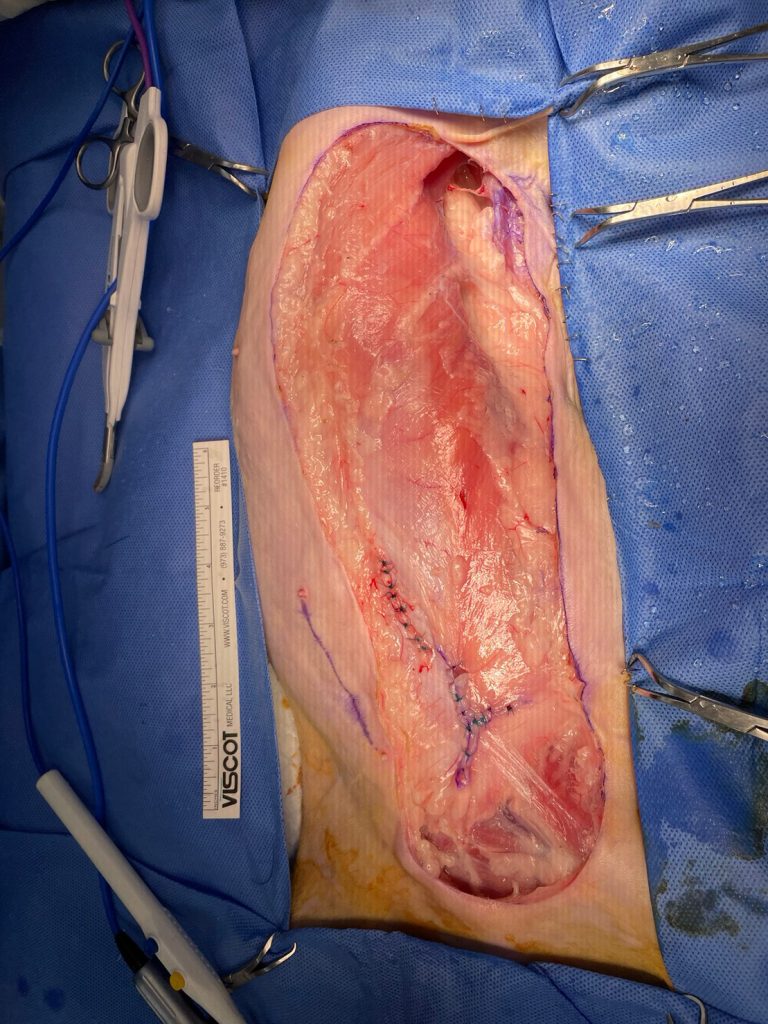

如同這張圖,左側乳腺以及淋巴結都已切除乾淨,幾乎看不見有地方在出血。

最後,我們將創口關閉,張力並不會太大,這表示術後貓應該會恢復得蠻順利的。

至此手術結束。